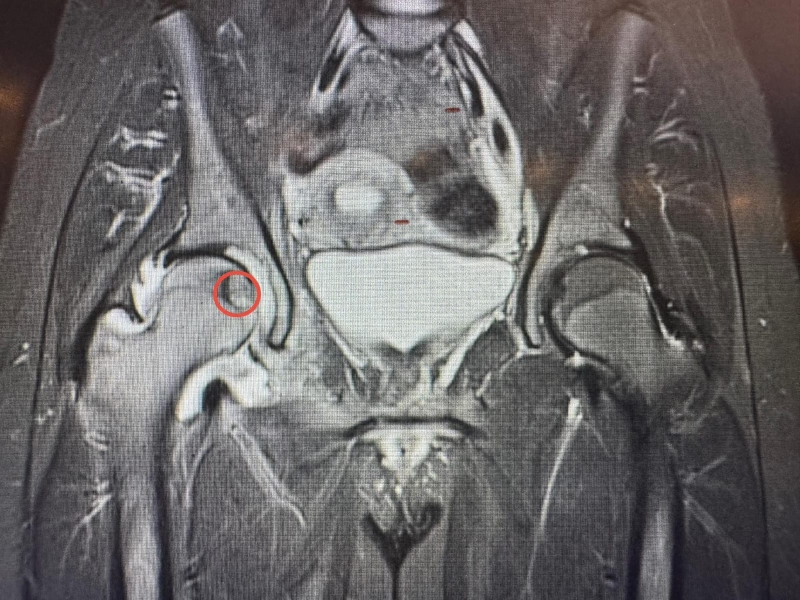

أجرى مستشفى الجامعة الأردنيّة، مؤخّرًا، تدخلًا علاجيًّا متقدّمًا في قسم الأشعة، استطاع من خلاله فريقٌ طبيٌّ متعدد الاختصاصات معالجة ورمٍ عظميّ في موقعٍ شديد الحساسيّة داخل رأس عظم الفخذ لمريضٍ ثلاثينيّ، ويُعد هذا الموقع من أكثر المواضع صعوبةً في الوصول إليها جراحيًّا، ما يجعل الخيارات التقليديّة محدودة ويزيد من تعقيد التعامل مع الحالة، لاسيما وأنّ المريض كان يُعاني من آلام حادّة أثّرت بشكل كبير على قدرته على الحركة وممارسة أنشطته اليوميّة.

وبيّن البطوش، أنّ الفريق الطبي نجح في الوصول إلى مركز الورم بدقة عالية باستخدام تقنيّة التصوير الطبقيّ المحوريّ (CT Scan)، تلا ذلك إجراء الكي بالتقنيّة الحراريّة باستخدام المايكروويف (Microwave Ablation)، وهي من أحدث التقنيّات العالميّة في علاج أورام العظام دون الحاجة إلى التدخّل الجراحيّ المفتوح.